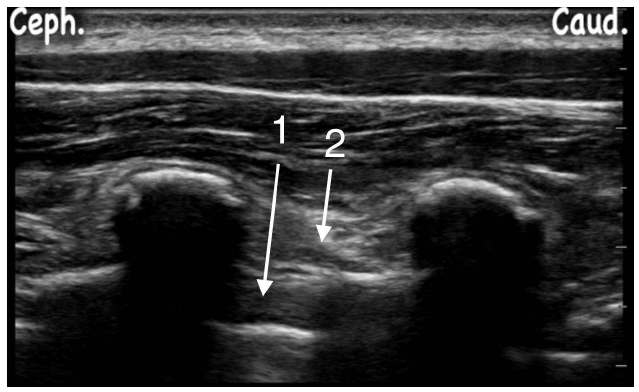

Observe a figura a seguir e assinale a alternativa CORRETA: